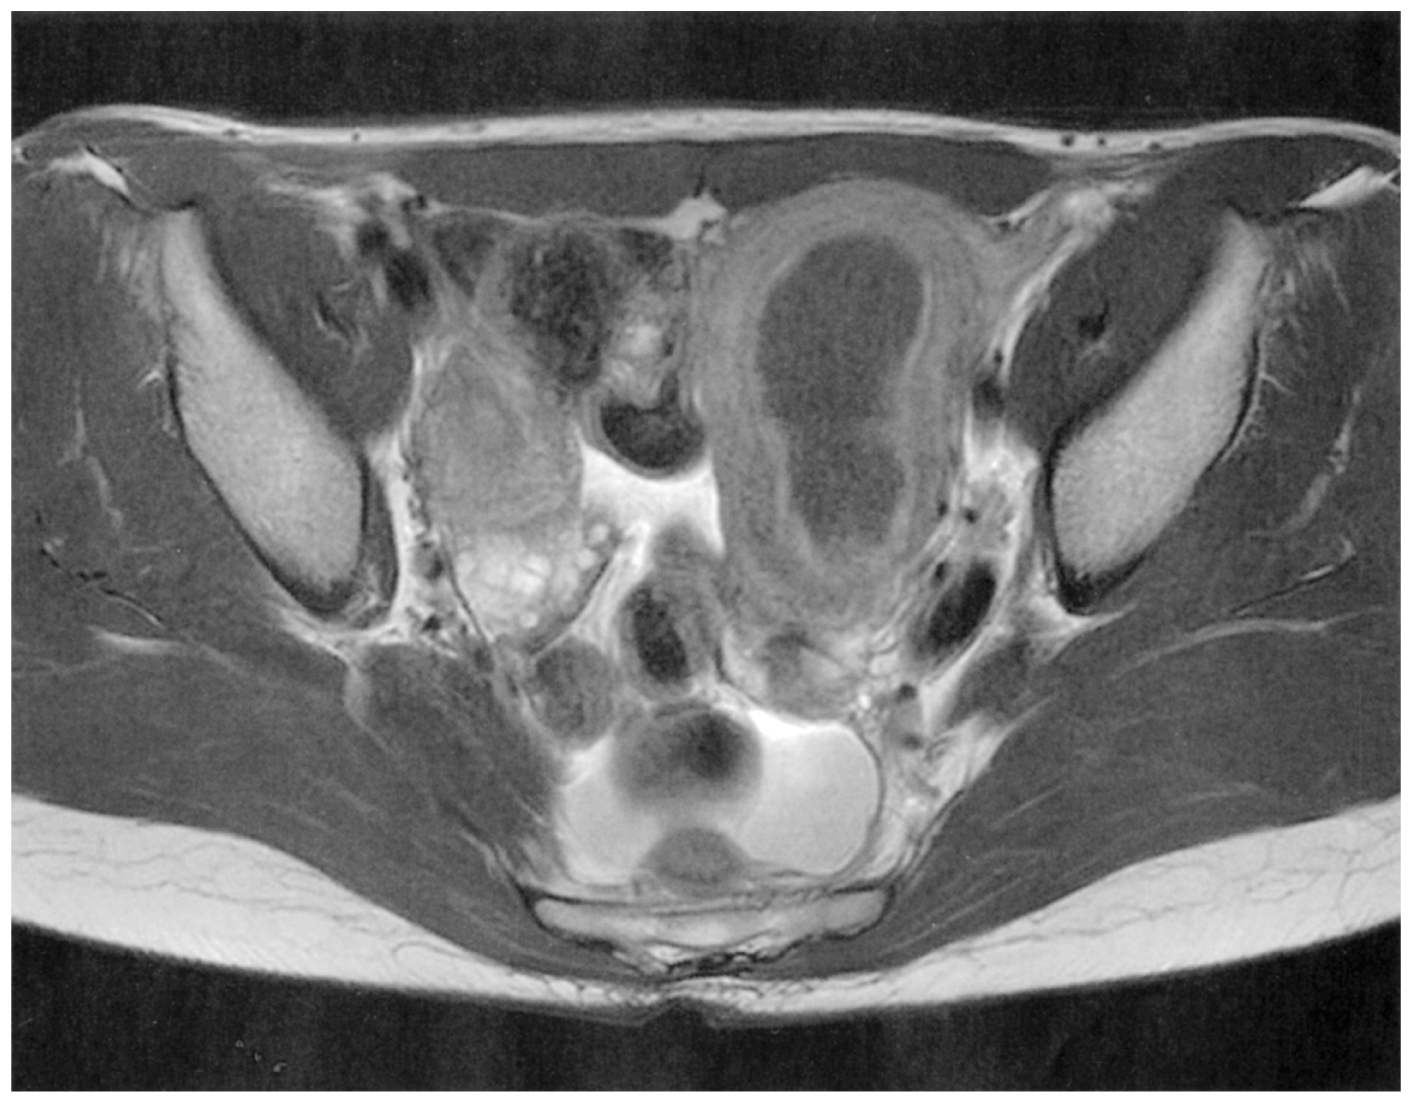

16歳の女子。毎月の月経時の強い下腹部痛を主訴に来院した。初経時より月経時の強い下腹部痛を自覚するようになった。月経時の下腹部痛が増強し,自宅近くの医療機関を受診したところ,左腎無形成と診断された。その後も毎月強い月経困難症が持続するため,紹介されて来院した。定期的な月経はあるが,毎回月経2~3日目に強い下腹部痛が出現し,鎮痛薬でも効果が乏しい。性交歴はない。初経は13歳。月経周期は28日型,整。経血量は正常範囲内である。体温36.0℃。脈拍88/分,整。血圧114/72mmHg。左下腹部に径10cmの腫瘤を触知し,付属器は触知しない。同部に圧痛を認める。骨盤部単純MRIのT2強調像を下に示す。